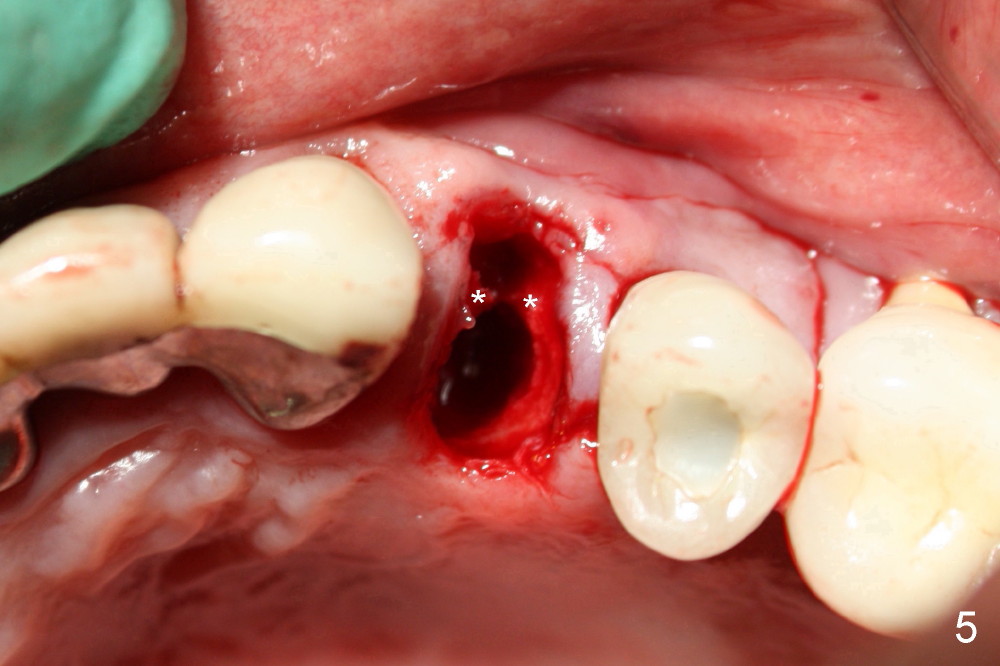

A 50-year-old man has mild pain in the upper left 1st bicuspid 3 years after root canal retreatment with placement of two posts (Fig.1). Findings of clinical exam are consistent with root fracture (Fig.2). Extraction reveals two fused roots (Fig.3,4). Probing indicates that the buccal plate is defective. Osteotomy is initiated in the palatal socket with a 2 mm pilot drill, followed by 2.5 and 3.0 mm reamers and 4.5x20 mm tap. The septum appears to have been pushed buccally (Fig.5 *) and form a new buccal wall (partially, strengthened by bone graft mentioned below) for the implant to be placed. The implant (4.5x20 mm) is placed in the palatal socket (Fig.6 *) with insertion of an abutment (A: 3.5x5 mm 0º), while a mixture of autogenous bone (harvested from reamers) and Synthograft (Bicon) is placed in the shrunken buccal socket (Fig.7; using allograft may decrease postop bony shrinkage). The bone graft is then contained by an immediate provisonal without collagen membrane or flaps. The patient is doing well postop. The gingiva is healthy (Fig.8*) when the provisional is removed 3 months postop with normal papillae (Fig.9 arrowheads). It remains the same 1 month post cementation (Fig.10,11). For further follow up, see immediate implant of the tooth #13.